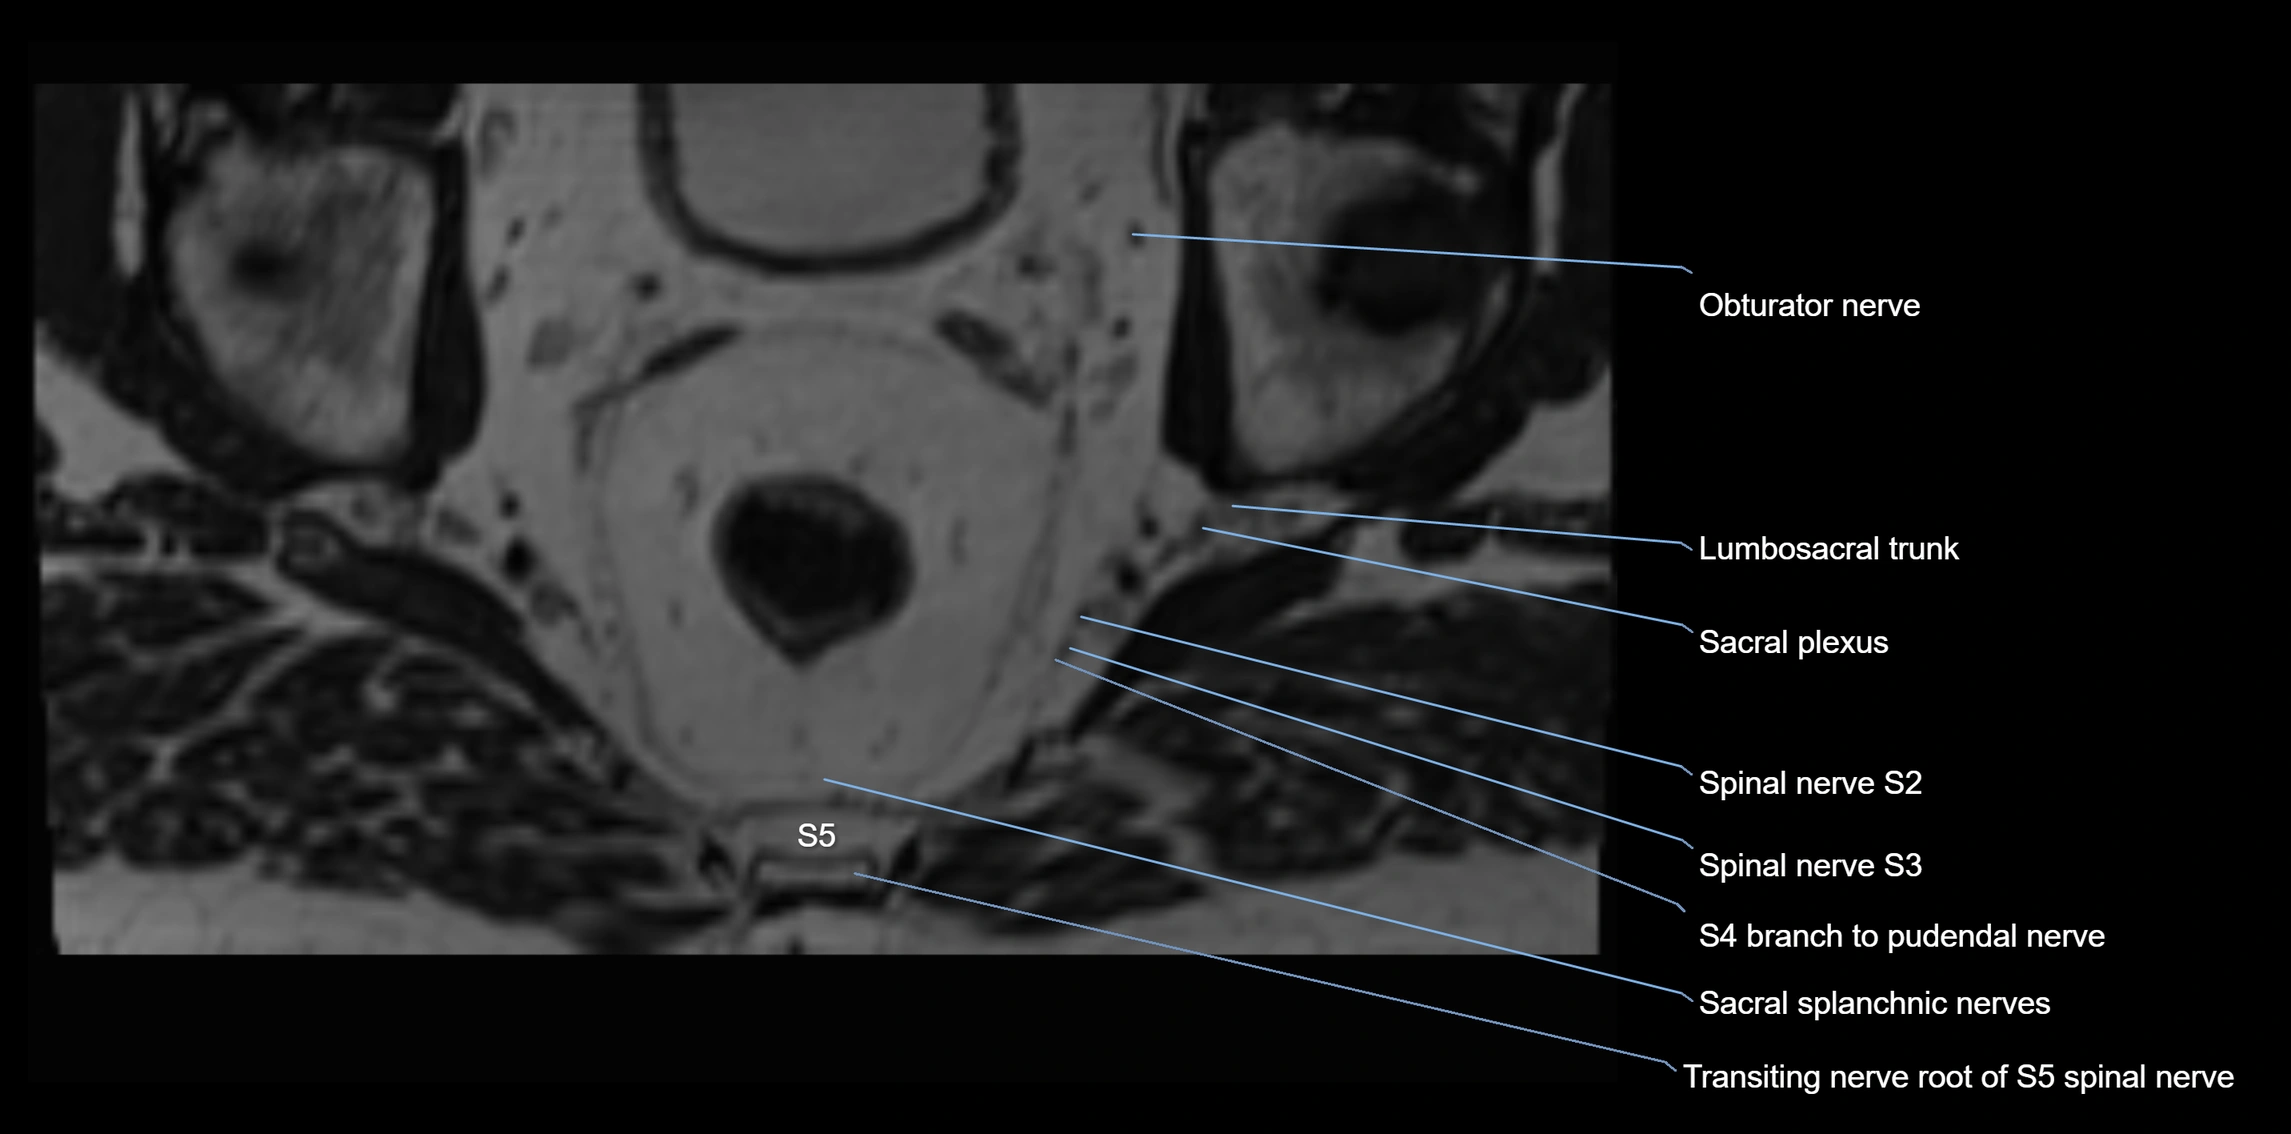

MRI Appearance

T1-weighted images:

• Nerve appears as a very thin low-to-intermediate signal intensity structure

• Surrounded by bright fat, aiding visualization

T2-weighted images:

• Nerve shows intermediate to mildly hyperintense signal compared to muscle

• Pathological involvement appears brighter

STIR (Short Tau Inversion Recovery):

• Normal nerve appears dark

• Inflamed or entrapped nerve appears bright hyperintense

T1 Fat-Sat Post-Contrast:

• Normal nerve enhances minimally

• Pathologic nerve (neuritis, entrapment, tumor infiltration) shows focal or diffuse enhancement

3D T2 SPACE / CISS:

• Nerve appears intermediate to mildly hyperintense compared to muscle

• Surrounded by bright fat or CSF, improving visualization

• Best sequence for mapping small pelvic nerves such as the anococcygeal

MRI image

image